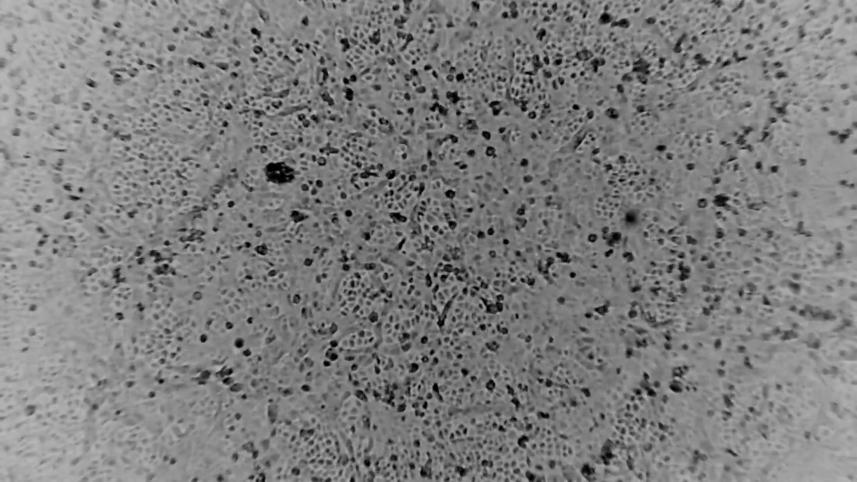

A team of scientists in Australia said on Wednesday they have successfully developed a lab-grown version of coronavirus, the first to be recreated outside of China, in a breakthrough that could help combat the global spread of the illness.

The researchers at the Peter Doherty Institute for Infection and Immunity in Melbourne said they would share the sample, which was grown from an infected patient, with the World Health Organization and laboratories around the world.

The virus was grown from a patient who had arrived at the institute on Jan. 24, it added.